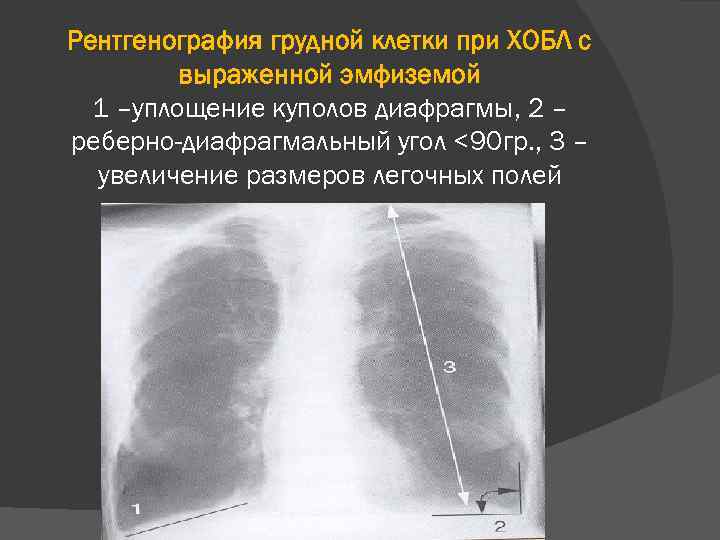

Рентгеновские снимки при врожденной эмфиземе легкого

Раздел: Визуальные уроки